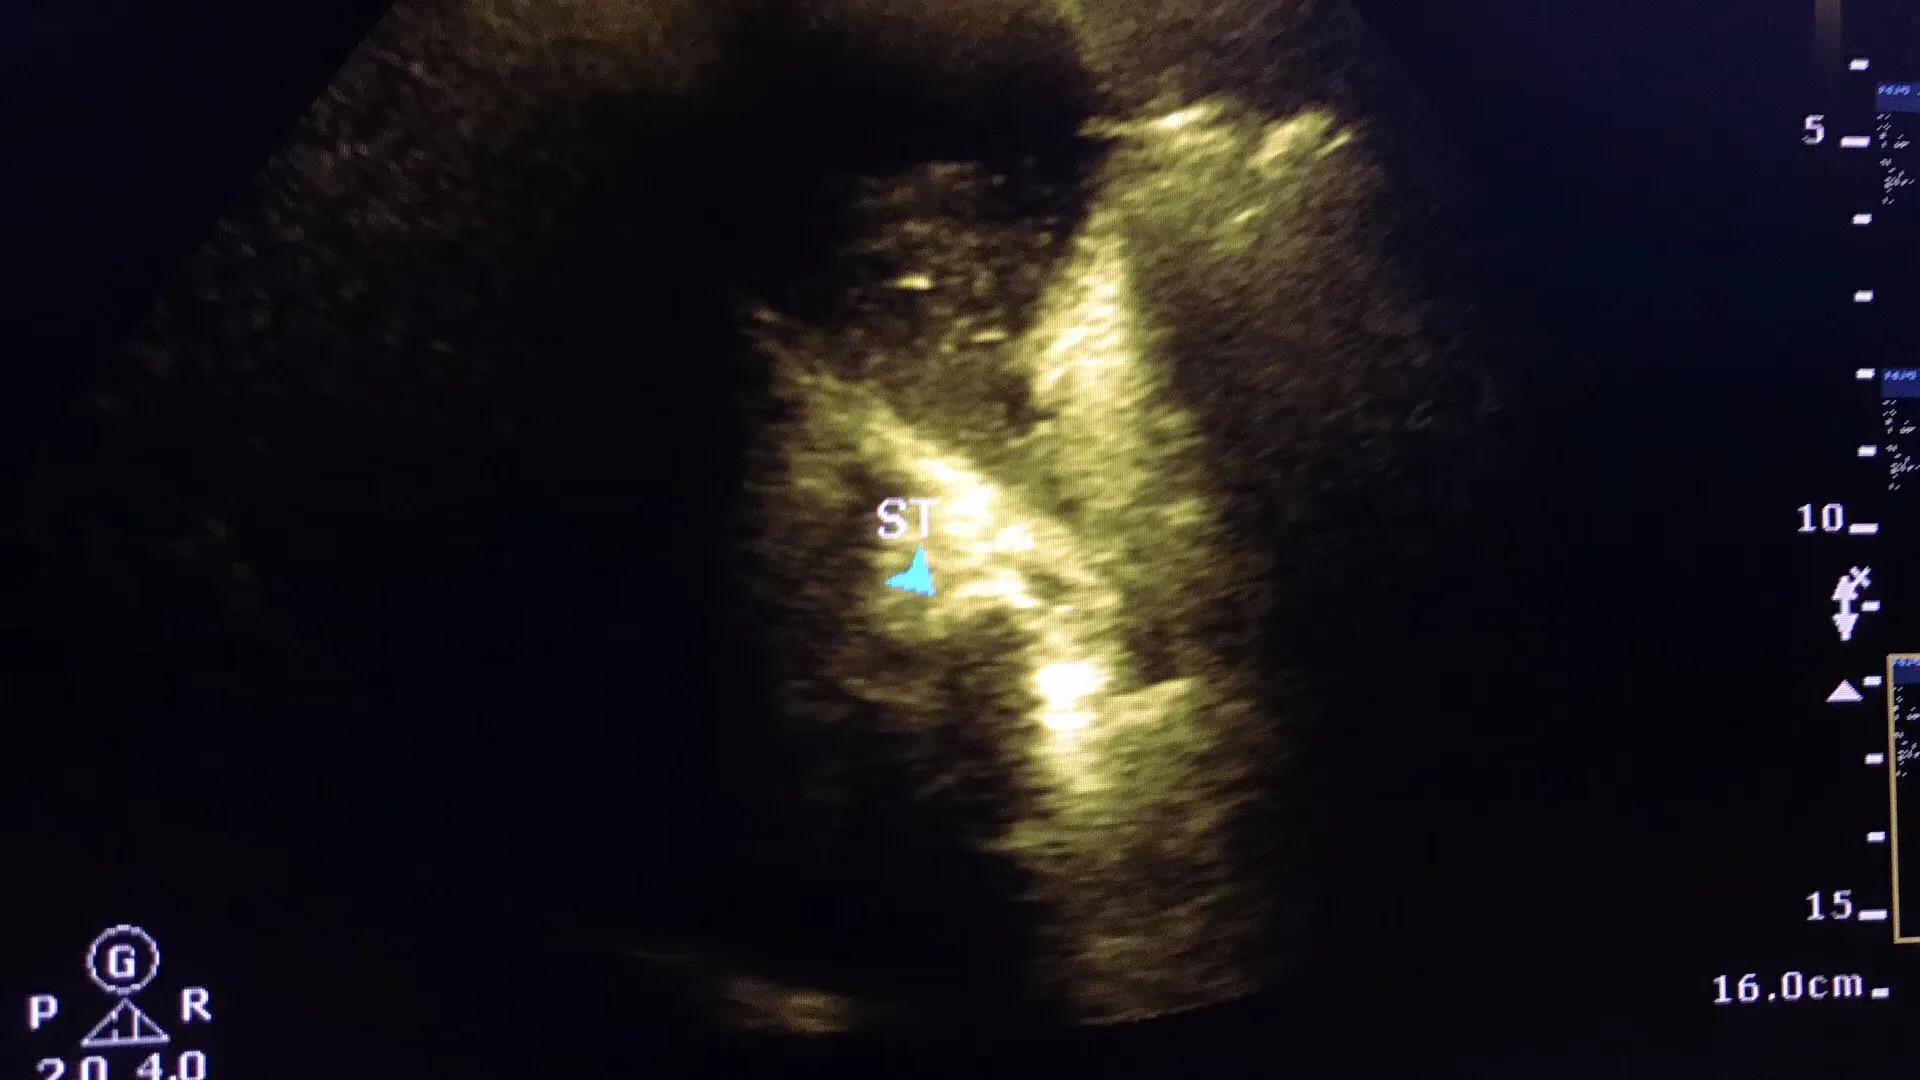

病例2.患者女性,63岁,胆囊颈部结石嵌顿继发急性胆囊炎胆囊穿孔!急诊手术证实胆囊穿孔!